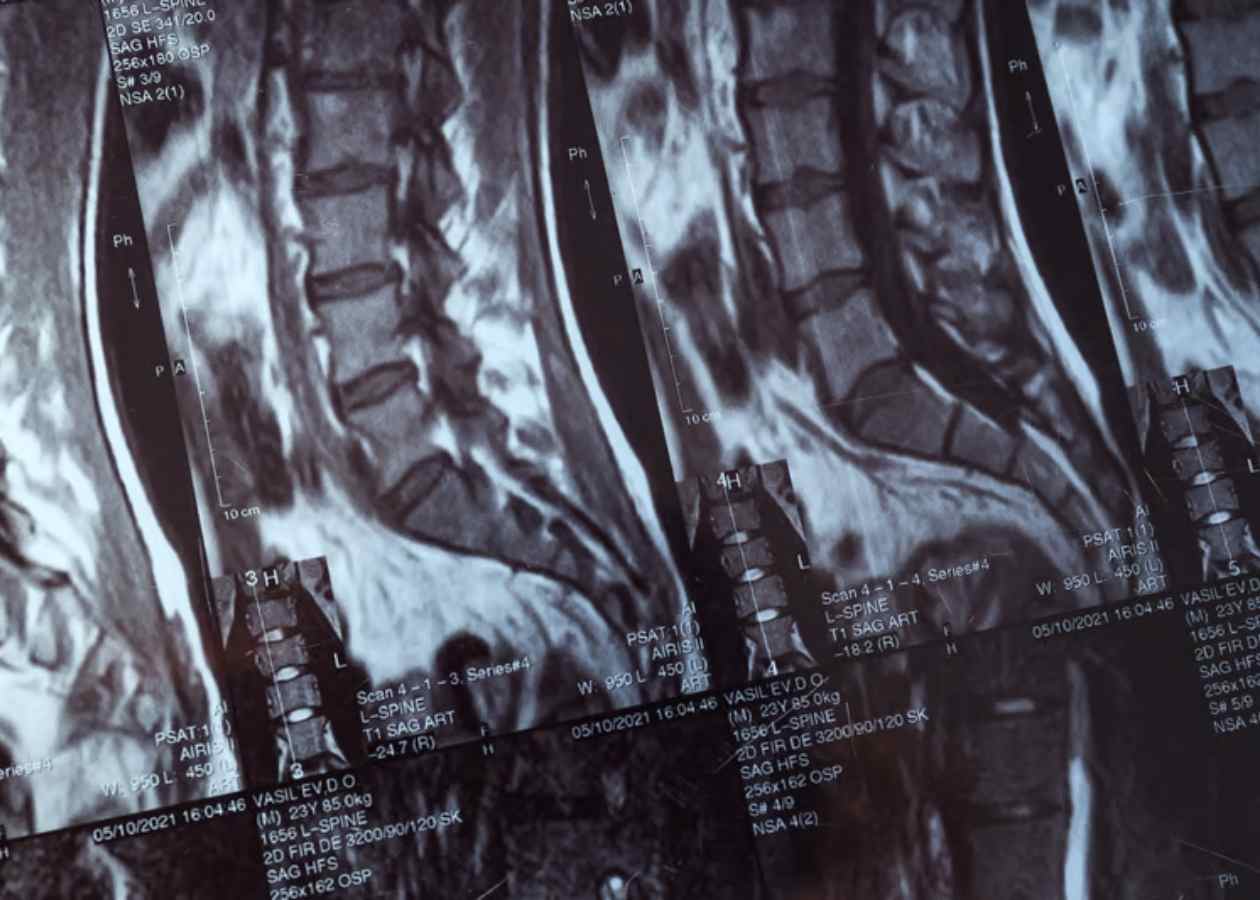

• MRG (Emar): Omurilik, sinir kökleri ve yumuşak doku yaralanmalarını değerlendirmek için altın standarttır.